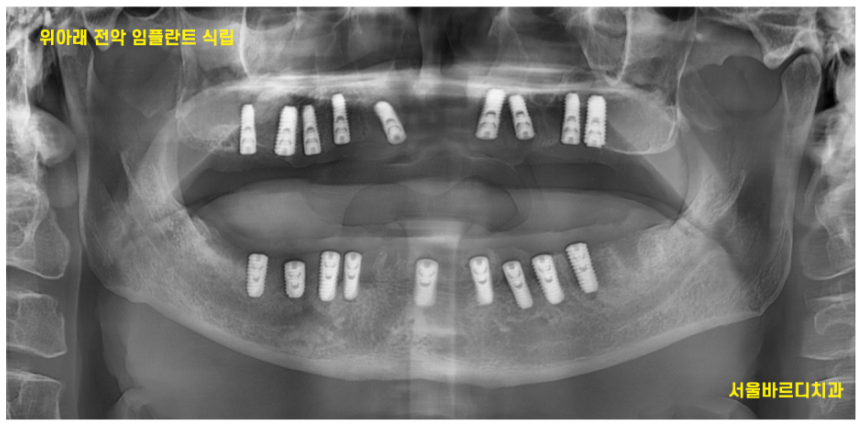

231023

엑스레이를 보면 이런 형태입니다.

임플란트 위에 작은 나사가 올라가있죠?

이게 힐링이에요

위에 환자분은 임플란트만 심겨져있죠~?